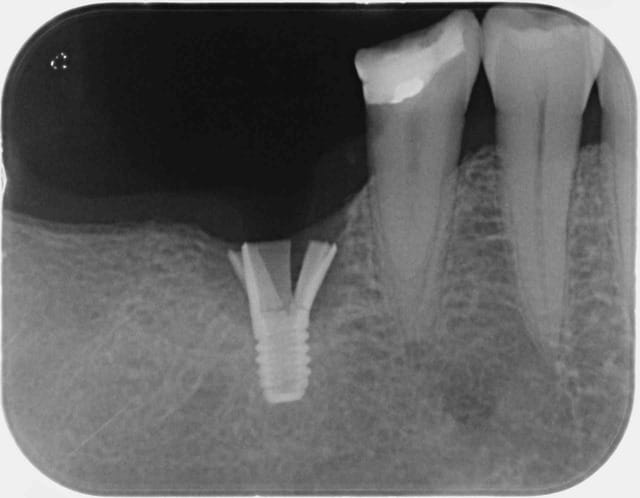

je sollicite vos avis sur ce cas atypique d'une fracture d'un col d'un implant Astra tech (Original), diamètre 4,5 et longueur 9mm, posé ya un an chez un patient, la couronne est de type transivissé sur un pilier Cast design.

Personnellement c'est la première fois que je vois un cas pareil, est ce que vous avez des explications sur les causes ? ou des cas similaires? confraternellement

mais bon, çà n'enlève rien au problème mécanique conceptuel de l'implant qui laisse une paroi haute et fine sur tout l'étage de la connexion...et le fait d'utiliser du titane grade 4 au lieu d'un alliage titane (TA6V) qui apporterait une résistance mécanique à peu près du double de la valeur actuelle...

intéressant, est tu certain qu'il s'agit d'un 4,5 de diamètre, il paraît minuscule. Et pourquoi un seul implant dans ce secteur de forte charge occlusale, vu l'édentement ?

Dans l'exemple en question ainsi que sur les références que tu as donné, l'implant est de faible diamètre et supporte bien plus de charge occlusale que pour ce dont il a été crée. Il aurait était judicieux de compléter par un deuxième implant ou au moins d'augmenter le diamètre.

Donc je ne pense pas qu'Astra soit en cause dans ce cas. Un implant Astra 4,5 qui remplace une 6 et une 7, c'est too much.

On ne remplace pas une molaire unitaire avec un diamètre 4.5 ASTRA (ou autre d'ailleurs) .